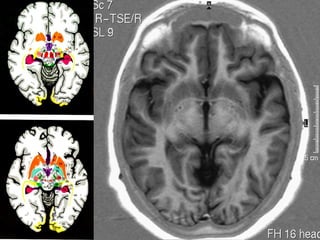

Anatomia cerebral

Gânglios da Base

• Tecido de substância cinzenta sub cortical

simétrico, localizados nas superfícies inferiores

dos hemisférios cerebrais.

• Núcleos lenticulares ( putamen e globus pálido),

núcleo caudado, claustro e amígdala.

Núcleos lenticulares.

• Biconvexo , envolto por substância branca,

• Cápsula externa ( separa do Claustro ),

• Cápsula Extrema ( separa claustro da ínsula ),

• Cápsula interna ( braço anterior , joelho e

braço posterior ).

• Putamen ( lateral , maior e mais escuro ) / globo pálido.

Núcleo caudado.

• Cabeça , corpo e cauda ,

• Cabeça é a principal parte , situada

adjacente ao corno frontal do VL.

• Separado incompletamente do n.

lenticulares pelo braço anterior da cápsula

interna ( feixes de Probst ).

• Cauda postero externo ao tálamo.

NÚCLEO

CAUDADO

cabeça

corpo

LENTIFORMES

putamen

Globo pálido

Amígdala.

• Pequena expansão da cauda do n. caudado,

• Complexo de vários pequenos núcleos ,

localizados na parte anterior do teto do corno

temporal do ventrículo lateral.